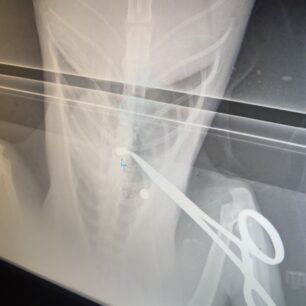

Το ζώο, όπως έδειξαν οι ακτινογραφίες, είχε πυροβοληθεί με αεροβόλο δύο φορές. Το ένα σφαιρίδιο είχε καρφωθεί στην σπονδυλική του στήλη και αν δεν είχε πάει επί τόπου ο εθελοντής διασώστης Κώστας Μαμασούλας, ώστε και να το πιάσει και να το μεταφέρει σε κτηνιατρική κλινική, η γάτα θα ήταν ήδη νεκρή και θα είχε μαρτυρικό θάνατο…

Οι πιθανότητες να περπατήσει είναι λιγες, ωστόσο αποφασίστηκε να κάνει το χειρουργείο και να του δώσουμε έστω αυτή την μικρή πιθανότητα ώστε να βγει η σφαίρα που είχε σφηνώσει στην σπονδυλική στήλη και να αποσυμπιεστεί. Τώρα το μόνο που μας μένει είναι να περιμένουμε, καθώς είναι πολύ δύσκολο ζώο και καθόλου συνεργάσιμο.».